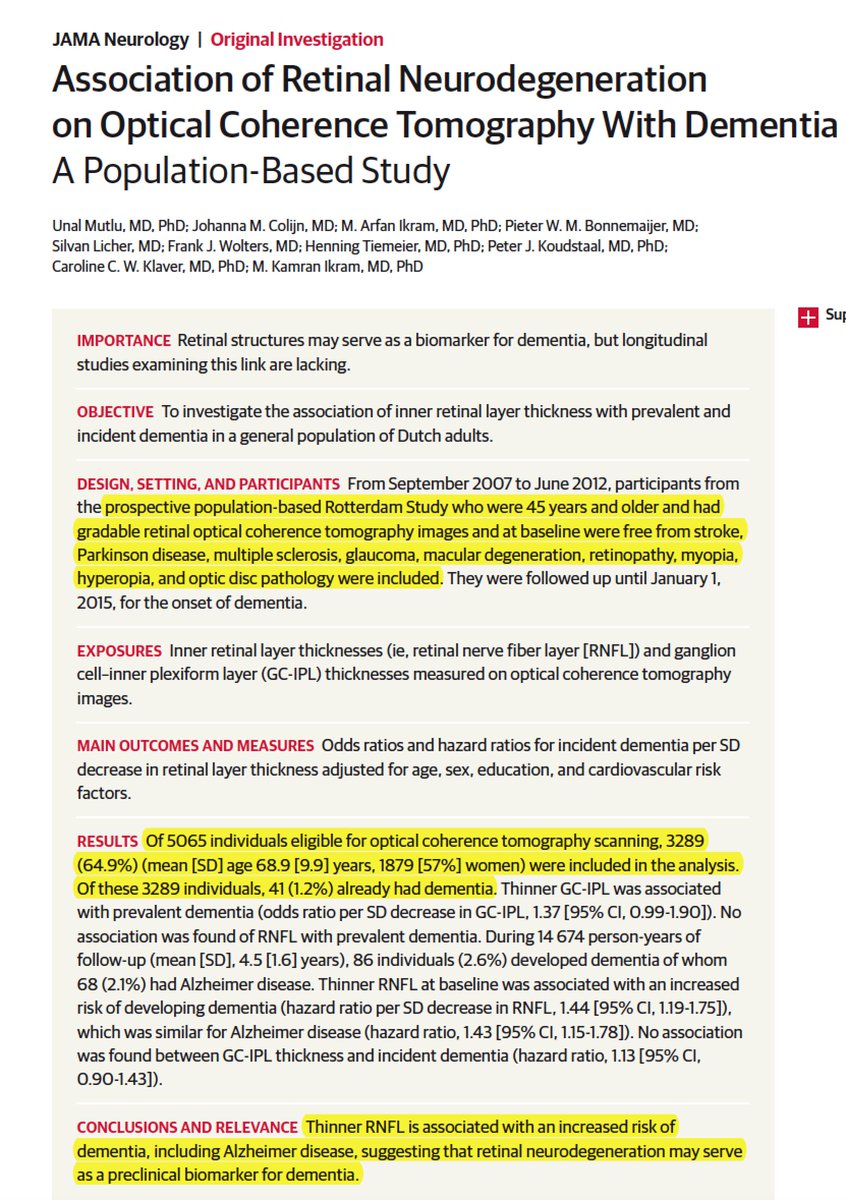

JAMAOphthalmology Retweeted

Retweeted from Eric Topol: Will your eye OCT exams be a window to cognitive decline in the future? https://jamanetwork.com/journals/jamaneurology/fullarticle/2685869 …

@JAMANeuro@erasmusuni@erasmusmc pic.twitter.com/tfPig520AB#medicinepic.twitter.com/ieniCNQoKh